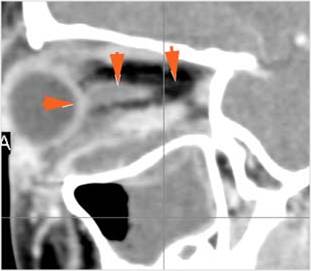

Orbits

The extraconal orbital fat is abnormal.

There is a subperiosteal abscess or edema along the medial wall, roof or floor of the orbit.

The extraocular muscles are swollen or otherwise abnormal.

There is bone erosion along the walls of the orbit.